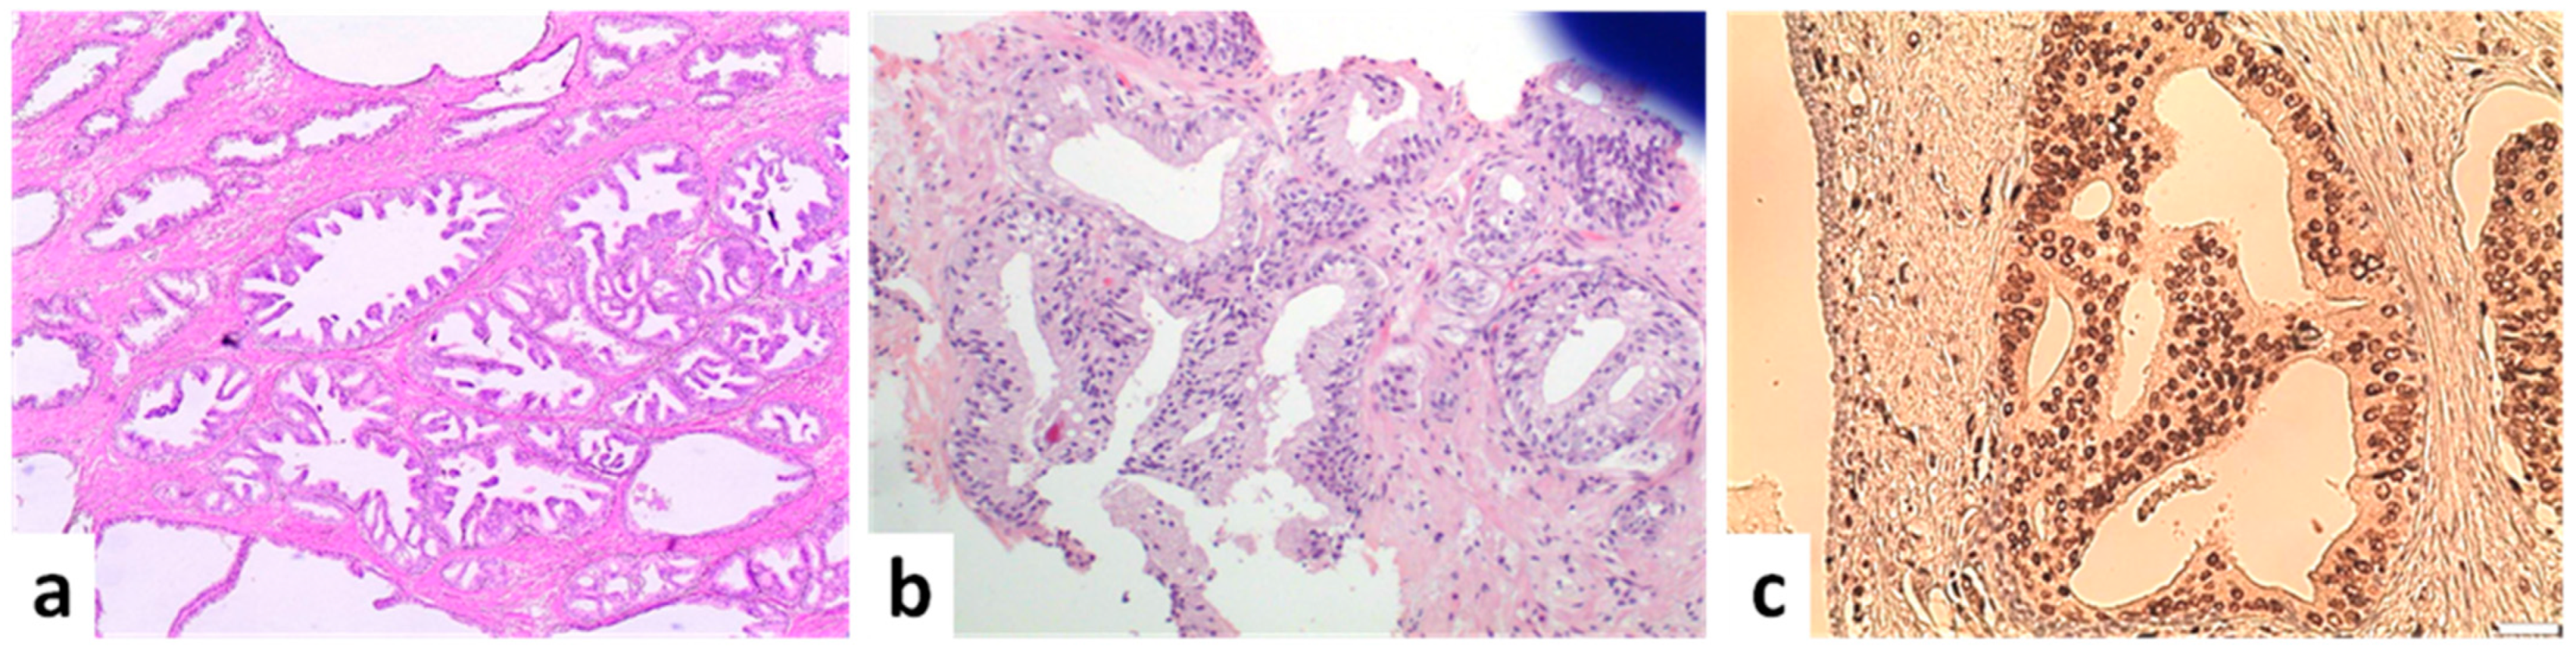

High-Grade Prostatic Intraepithelial Neoplasia (HGPIN)

5.1. Intraductal Carcinoma (IDC)

5.2. Invasive Acinar Carcinoma with Cribriform Pattern

5.3. Ductal Carcinoma